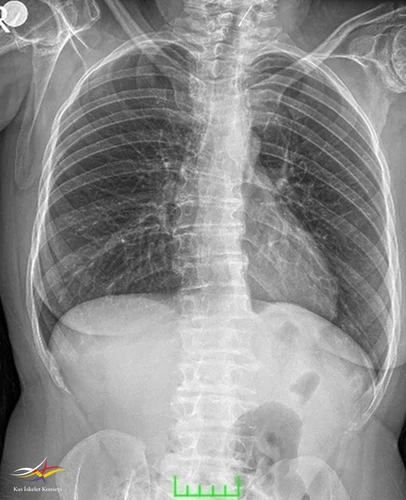

Resim 1.

- Klinik Özellikler: Kısa boy-kısa gövde: Özellikle ergenlik öncesi veya ergenlik döneminde gelişir. Gövde kısalığı ve fıçı göğsü belirgin olabilir. Her iki kol uzunluğu boy uzunluğundan fazla olur

- Radyolojik Bulgular

2. Epifizyal değişiklikler: Uzun kemiklerin epifizlerinde irregular yapı, morfolojisi bozulmuş epifizler.

Femur başında: Kısa femoral boyun, coxa vara, kalça çıkığı veya düzensiz epifizyal konturlar.

3. Ek bulgular: Omurga büyümesi normal doğumdan sonra başlar, ancak ergenlik öncesinde yavaşlar.